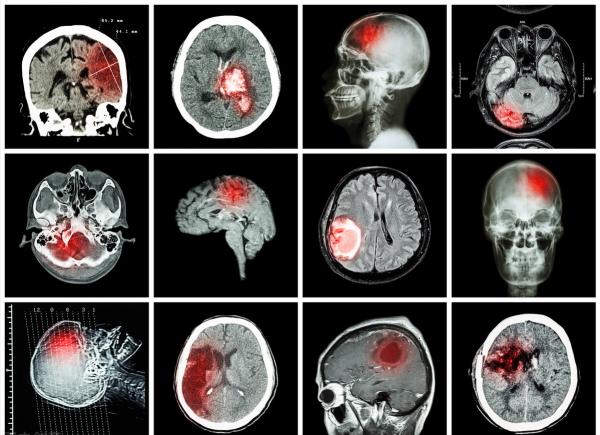

高血壓,歸屬於中醫學“頭痛”、“眩暈” 等範疇,病機多為肝腎陰陽失調。實者多為初期肝火亢盛、痰溼壅盛。病久傷陰多為陰虛陽亢、肝腎陰虛。二者相互影響,致使病情遷延不愈,虛實夾雜。中成藥不但可有效改善高血壓症狀,還能從根源上多角度調和機體陰陽平衡,釜底抽薪,各個擊破。